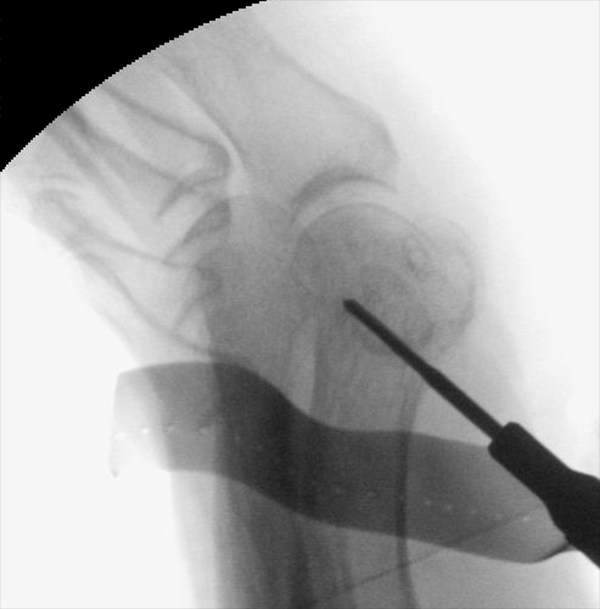

• Positionierung des Bildwandlers: 90° Winkel zum Os metatarsale I. Benötigt wird die Durchleuchtung des Vorfußes a.p., seitlich und schräg.

Operationstechnik

Der von Isham/Reverdin beschriebenen minimal invasiven Technik zur Korrektur einer Hallux valgus Deformität liegen 4 Operationsschritte zu Grunde:

1. Abtragung der Exostose am Köpfchen des 1. Mittelfußknochens

2. Subcapitale intraartikuläre Osteotomie

3. Laterales Release

4. Akin Osteotomie der Großzehengrundphalanx

Die Folge der Operationsschritte sollte strikt von 1. - 4. erfolgen, da ansonsten die mediale Closing Wedge Osteotomie bei vorzeitigem lateralem Release und/oder Akin Osteotomie nicht geschlossen werden kann. Nach der von Isham beschriebenen Originaltechnik finden Implantate keine Anwendung, zur Sicherung und besseren Fixation können osteosynthetische Verfahren angewandt werden (siehe auch Fehler, Gefahren und Komplikationen).